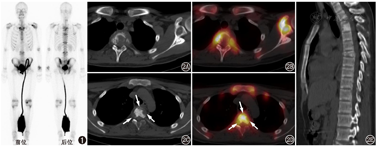

患者男,17岁,2020年1月无明显诱因出现左侧桡骨远端疼痛,后发现左桡远端肿块,并逐渐出现弯腰受限。2020年5月患者出现双下肢无力,2020年6月中旬出现发热,体温最高38 ℃,不伴畏寒、寒战、盗汗。查血常规、肝肾功能大致正常,血结核感染T细胞检测阳性(2.619 kU/L),抗核抗体(antinuclear antibody, ANA)、抗可溶性抗原(extractable nuclear antigen, ENA)、抗中性粒细胞胞质抗体(anti-neutrophil cytoplasmic antibodies, ANCA)、抗环瓜氨酸肽(cyclic citrullinated peptide, CCP)抗体均阴性,多次血培养及骨髓培养(-),血、尿免疫固定电泳(-),血游离轻链比值(-)。外院腕关节MRI示左桡骨远端占位,大小2.7 cm×1.8 cm×2.3 cm,伴周围软组织水肿;髋关节MRI示双髂骨、耻骨、髋臼及左侧股骨颈多发异常信号,考虑"骨肿瘤"。外院18F-FDG PET/CT显像示左侧桡骨远端、左侧肩胛骨、C4椎体、T3~T4、T7、T11、L3椎体、骨盆多处、左侧股骨颈、左侧股骨内侧髁多发溶骨性破坏,代谢异常增高(SUVmax:28.5~32.8)。随后完善桡骨穿刺,病理示多量组织细胞及少量淋巴细胞,免疫组织化学:组织细胞CD68(+),CD1a(-),Langerin(-),S-100蛋白(-),细胞增殖核抗原Ki-67(约20%),考虑组织细胞增生性病变,首先考虑Erdheim-Chester病(Erdheim-Chester disease, ECD),B-Raf原癌基因丝/苏氨酸蛋白激酶(B-Raf proto-oncogene, serine/threonine kinase, BRAF)V600E野生型。2020年6月起予干扰素、泼尼松治疗,患者每日仍有低热,且双下肢无力逐渐加重,无法站立,伴尿潴留。后患者为进一步诊治入本院,为评估骨病变行99Tcm-亚甲基二膦酸盐(methylene diphosponate, MDP)全身骨显像及胸部SPECT/CT显像(图1,图2)。全身骨显像示颈、胸、腰椎多个椎体、左侧肩胛骨、双侧骶髂关节、右侧髋臼及坐骨、左侧腕关节、左侧膝关节显像剂摄取增高灶,SPECT/CT显像可见这些病灶部分为溶骨性破坏,也有部分是成骨为主的骨破坏,部分椎体病变周围伴有软组织密度影,另外有多个椎体出现病理性骨折。

本例是以骨骼多发病变为主的病例,外院已行病变活组织检查(简称活检)并且有了较为明确的病理诊断,考虑为ECD。所以我们要考虑的问题就是,这个病例的骨显像以及其他临床特点是否符合ECD表现?ECD属于组织细胞增生症,与朗格汉斯组织细胞增生症(Langerhans cell histiocytosis, LCH)不同,ECD是非朗格汉斯组织细胞疾病,可能来源于单核巨噬细胞系。ECD可累及全身多个系统,最常受累的是骨骼系统,占95%;几乎所有ECD骨受累的图像都表现为以四肢长骨骨干为主的、对称性的骨质硬化和成骨性病灶,大多累及干骺端,并且以下肢更为多见,其次也可累及颅骨(颌面骨为著),脊柱和骨盆骨也可受累[1]。骨显像上ECD最典型的表现为双侧股骨远端、胫骨近端及胫骨远端弥漫性、对称性摄取增高(图3)。本例患者骨骼病变以中轴骨为主,并且病变大多伴明显的溶骨性破坏,和ECD的骨病特点不相符。其次,ECD一般是多系统受累,很少出现单系统病变,除骨骼系统外,心血管系统、肺、肾周、中枢神经系统(眼眶、垂体为主)、皮肤等亦是ECD常累及的部位,而本例患者在外院行18F-FDG PET/CT显像,临床和影像都没有发现骨骼系统以外的病变证据。ECD患者的症状一般与累及的系统有关,如可出现骨痛、胸闷、突眼、尿崩等症状,患者病程中很少出现发热,并且ECD好发于中老年人,本例患者的年龄、发热病程亦不典型。ECD的治疗首选为干扰素,有时会辅助糖皮质激素,但本例患者在经干扰素和糖皮质激素治疗后症状却逐渐加重。综上,本例无论是骨骼病变的影像特点还是临床特点,都不支持ECD的诊断。